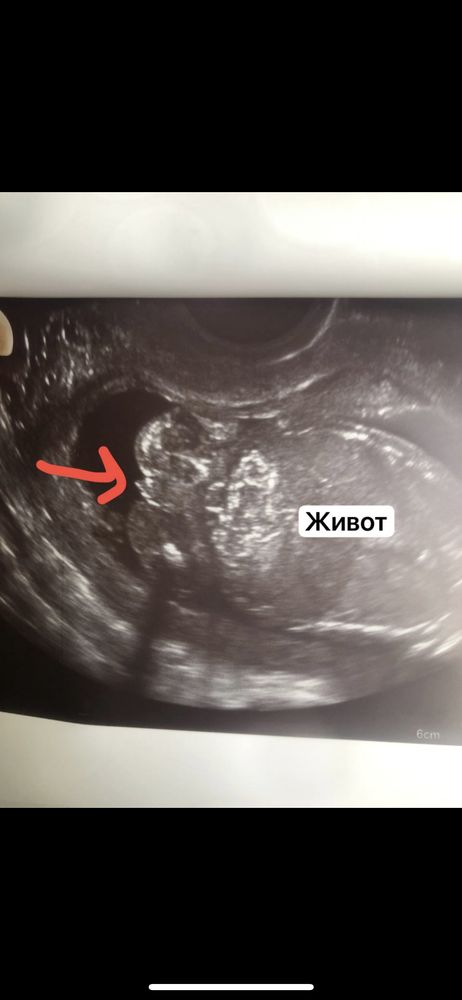

Девочка у Вас. И то, что Вы подписали "живот" - черепушка ребёночка, вообще-то😉😊 А "распухшие губы" (по Вашему описанию) - это попа. Смотрите то, что мельче😇🙈

МиниМама, я знаю где там что , узист мне показывала , это именно живот , попка и то что между ней ) пол смотрела трансвагинальным датчиком . Поэтому это не череп , узист описывала

Алена, как хотите. Я написала, что вижу на снимке😊 А по сабжу: У меня по крови с детьми ошибок не было. С дочкой сдавала в 10,4 недель. С сыном - в 11

Мисс Драма, аппарат экспертного класса . Она как бы показывала «это место» там действительно не понятно , то ли мальчик , то ли девочка с распухшими губами ….

Мисс Драма, а вот и хрен знает кто тут 😂 стрелочкой отметила Изображение

Узи 15 недель и три дня, определение пола ребенка Кровь на пол)